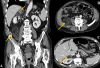

Case presentation: We report a very seldom case of a simultaneous myelolipoma of the adrenal gland in association with an extra-adrenal myelolipoma in an 75-year-old man. With a review of the literature we describe and discuss the aetiology, differential diagnosis and treatment of patients with respect to adrenal and extra-adrenal lesions.

Conclusion: The appearance of a simultaneous adrenal and extra-adrenal myelolipoma is a rare incident. We conclude that such lesions should be considered in the differential diagnosis of a fat-containing tumour in the retroperitoneal tissue/compartment.